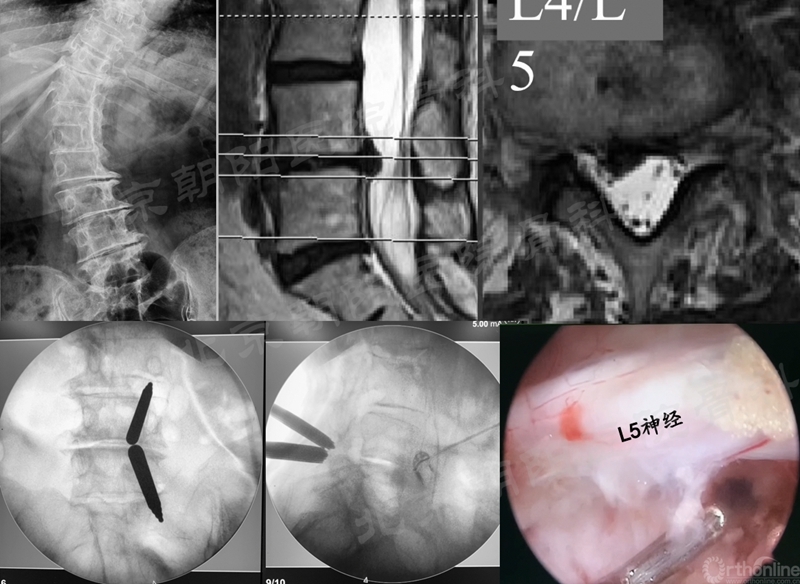

#10例UBE, L4/5 LSS。

#9例UBE,ADS合并L4/5LDH。

在经历15例UBE减压手术的学习曲线后,本团队进行了UBE腰椎减压融合术:#16例UBE,L4/5 LSS。